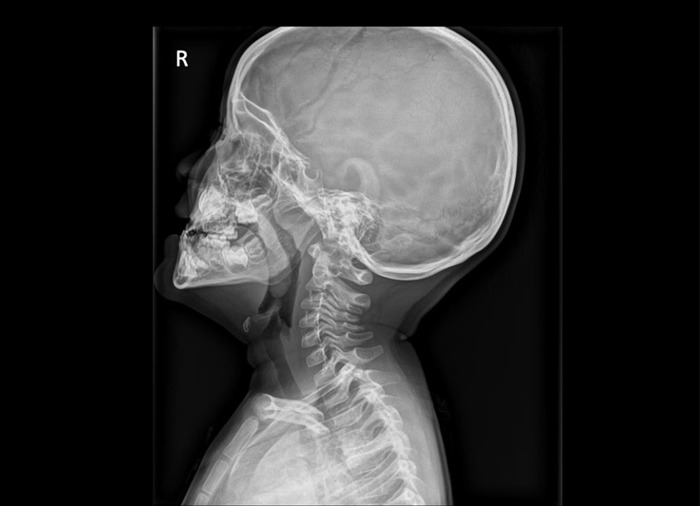

아데노이드는 코 뒤쪽과 목 사이에 위치한 림프 조직 덩어리로, '인두편도'라고도 불린다. 보통 흔히 말하는 편도는 목젖의 양쪽에 위치한 구개편도를 의미하지만, 아데노이드는 이보다 깊숙한 곳에 있어 눈에 보이지 않는다.

구강 및 기도가 좁아지면서 만성적인 코막힘과 입으로 숨을 쉬는 구 호흡이 나타나며, 만성 부비동염이나 중이염이 생기는 것이 가장 흔한 증상이다.

아데노이드 비대증을 방치하면 입으로 숨을 오랜 기간 쉬게 되면서 얼굴 길이가 길어지는 등의 안면골 변형도 드물게 나타날 수 있다.